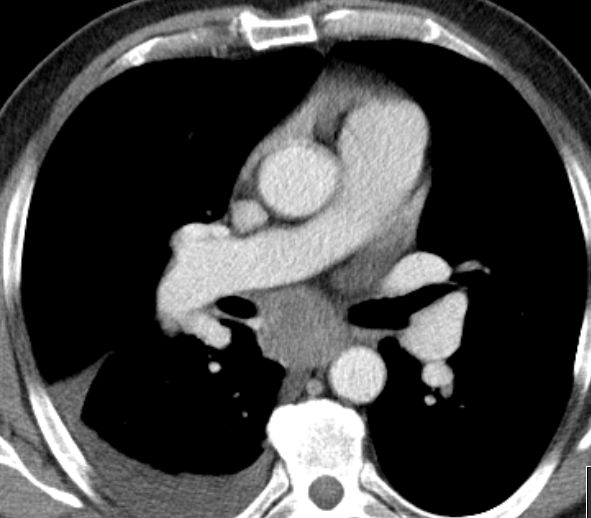

| Lymphknoten Karina | Die Karina wird durch eine große LK - Metastase

aufgespreizt.![]() |